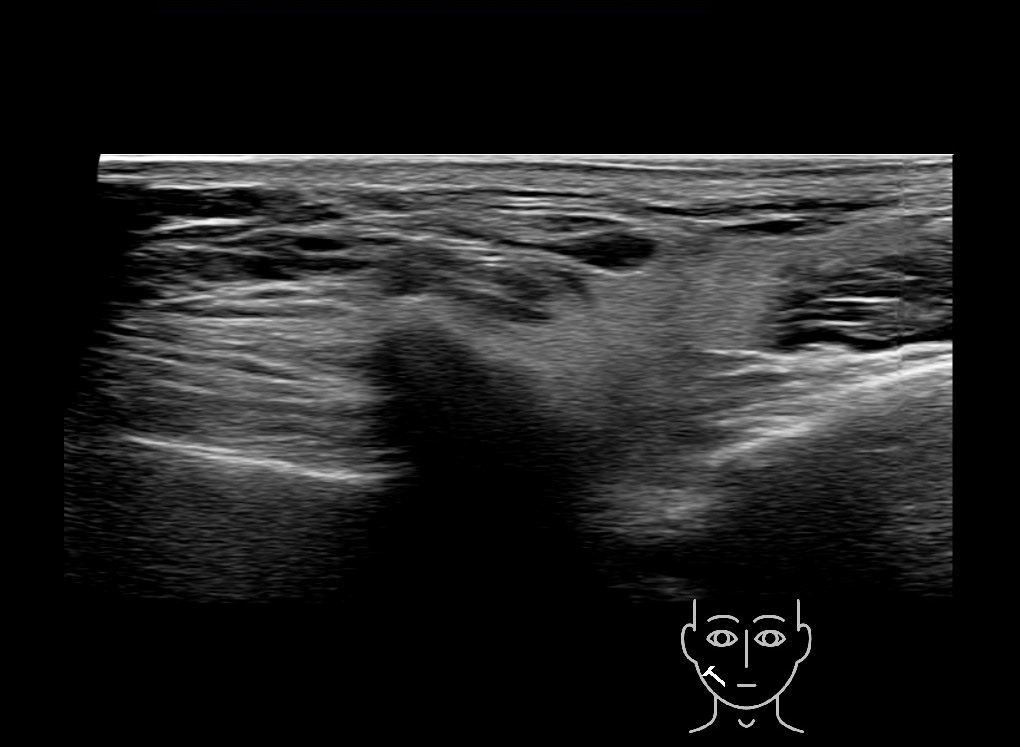

Study the first image to recognize the different layers. If you are sure about the layers, swipe to the second image to view the answer (if applicable).